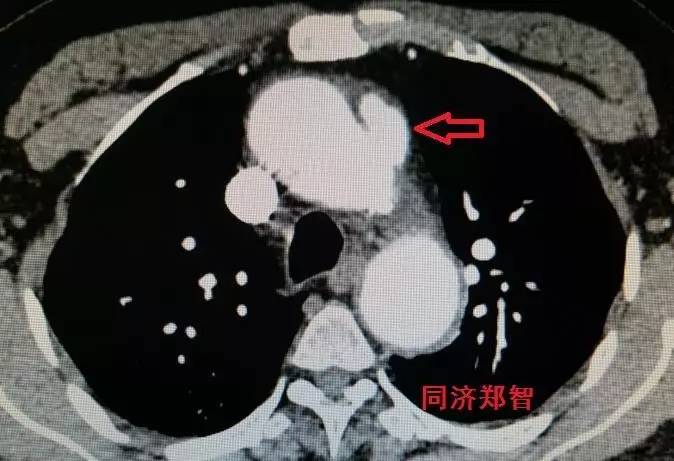

CTA轴位片显示主动脉弓穿透性溃疡(图11)。

图11